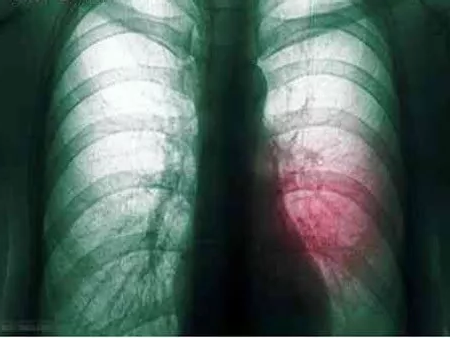

我院呼吸科主治醫(yī)生孟醒在分析2位患者的胸部CT結(jié)果并結(jié)合了解他們的生活史后,診斷他們得了肺膿腫。

在得知診斷結(jié)果后,兩位患者以為自己得了肺癌,不知所措,甚至感覺人生走到頭了。在此,孟醒提醒:肺膿腫和肺腫瘤完全是兩個不同的概念,大部分通過抗生素治療即可痊愈。

“肺膿腫是一種良性的肺部感染性疾病,由于病原菌多為厭氧菌,所以痰液常常帶有腥臭味。”孟醒介紹,在新中國剛成立前后,肺膿腫還是比較常見的,隨著人們生活水平的不斷提高,衛(wèi)生條件的不斷改善,現(xiàn)在得肺膿腫的病人已經(jīng)很少了。

他進一步解釋,既然肺膿腫是一種感染性的病變,只要根據(jù)痰液細菌培養(yǎng)的結(jié)果,選擇敏感的抗生素,肺膿腫就是可以治愈的。肺膿腫如長期(大于3個月)內(nèi)科保守治療效果不佳,或存在惡性腫瘤、大咯血、膿胸,則需要外科手術(shù)治療?!霸谖夜ぷ魇嗄陙?,從來沒有一例肺膿腫患者需要外科手術(shù)治療的?!泵闲烟嵝褟V大市民,吸煙有害健康,預(yù)防肺膿腫最好要戒煙,增強機體免疫力,同時要注意口腔衛(wèi)生,防止誤吸口、鼻、牙齦炎癥形成的膿性分泌物和嘔吐的胃內(nèi)容物等,此外,肺炎早期要積極給予抗生素治療。